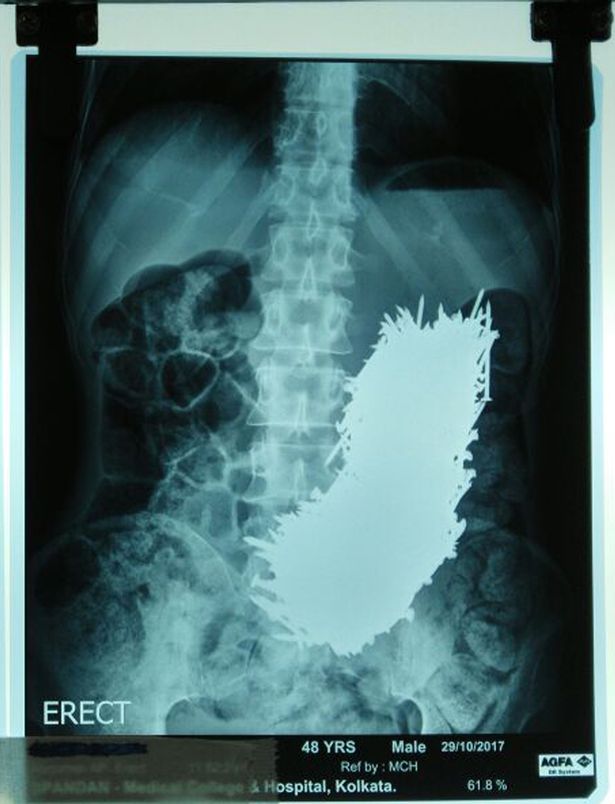

Kumar Dhali, 48 tuổi, đã nuốt 600 đinh sắt vào bụng

Pradip Kumar Dhali, 48 tuổi, được gia đình đưa đến bệnh viện sau khi ông bị đau bụng cấp tính. Sự việc xảy ra cách đây khoảng hai tháng nhưng mới được công bố gần đây, Mirror đưa tin.

Các bác sĩ đã sốc khi thấy ảnh chụp siêu âm với tổng cộng 600 đinh sắt trong bụng. Sau 2 ngày quan sát, họ quyết định dùng nam châm trong quá trình phẫu thuật, hút đinh sắt ra khỏi bụng bệnh nhân.

Ảnh chụp cho thấy số đinh khổng lồ trong bụng của Pradip